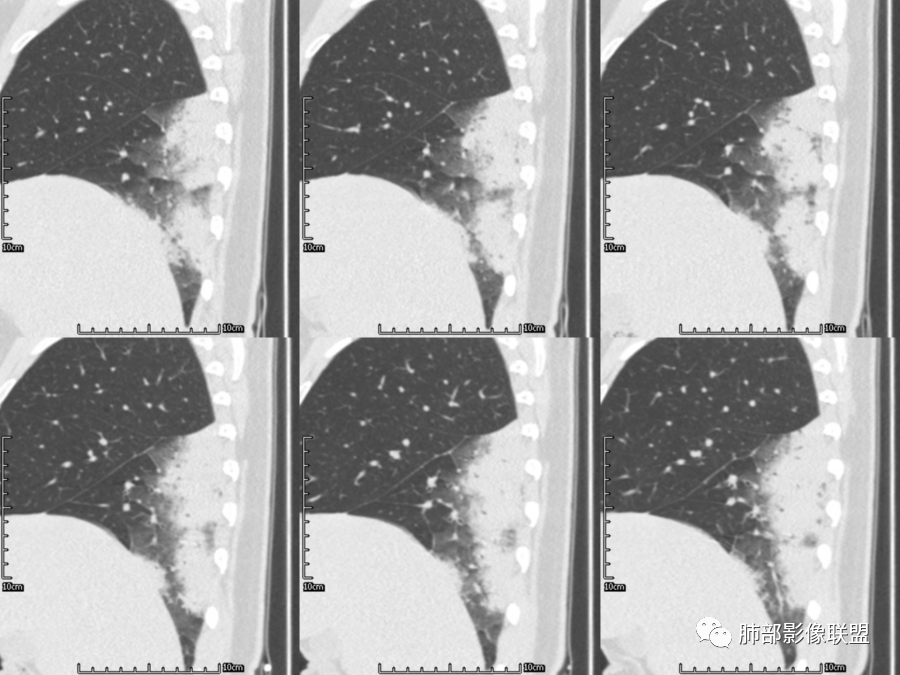

右肺胸膜下实变,病变跨多个叶生长,宽基底与胸膜相连,近端支气管穿行病灶内,并可见片状磨玻璃影,边界清,部分远端小支气管堵塞,支气管略有扩张,周围散发小结节,临床年轻女性,炎性指标高,发热六日,首先考虑感染性病变(肺链,奴卡,隐球,OP)鉴别淋巴瘤。

年轻女性,无明显诱因发热,体温略高,起病较急,有畏寒,右下肺紧贴胸膜下片状实变影,部分融合,外围有结节影,性质比较单一,类似于蘑菇兄弟,病灶周围伴有晕,支气管进入近端扩张远端堵塞,常规考虑感染,肺炎链球菌、隐球菌。

青年女性,发热咳嗽5天,炎症标志物升高。右肺下叶大片实变伴周围GGO,GGO内未见细网格,主体与胸膜平行,似多个病灶融合,实变区内见支气管部分进入,部分支气管受压狭窄,周围可见多发卫星病灶。支持炎性,考虑隐球感染,鉴别op。

年轻女性,急性起病,咳嗽,发热,黄痰,白细胞高,CRP基本正常,基础体健。CT提示右肺下叶实变,宽基底与胸膜相连,长轴平行于胸膜,可见支气管充气征,于病变中央截断,走形自然,胸膜下脂肪间隙可见,倾向于隐球菌,鉴别肺链,军团菌等。

年轻患者,右肺下叶大片状实变影,长轴与胸膜平行,内见含气支气管征,周围磨玻璃晕影。考虑感染性病变,隐球?

病灶长轴与胸膜平行,边缘有晕,病灶融合趋势,支气管进入,走行自如,考虑隐球菌肺炎。

年轻女性,急性发病,咳嗽咳痰五天,炎性指标升高,右肺下叶胸膜下大片实变影,周围见磨玻璃影,边界清晰,长轴与胸膜平行,呈融合趋势,支气管进入走行自然,远端截断,考虑炎性,隐球菌可能。

年轻女性,发热,急性发病,白细胞高,右肺下叶大片实变,长轴与胸膜平行,内见支气管走行,远端截断,周围有晕,晕边界清,考虑感染,隐球可能,鉴别淋巴瘤。

年轻女性,右肺下叶胸膜下多发实变、结节影,宽基底与胸膜相连,边缘模糊不清,实变内见支气管穿行,血象高,考虑感染性病变,大叶性肺炎?隐球?

青年女性,发热咳嗽急性起病,右肺下叶大片状实变密度影,长轴平行于胸膜,边缘模糊可见磨玻璃影及高密度结节影,实变内可见支气管穿行,直达病灶远端,考虑感染性病变,隐球菌可能大。

右肺胸膜下实变,病变跨多个叶生长,相互融合,宽基底与胸膜相连,支气管气象,并可见片状磨玻璃影,边界清,炎性指标高,发热六日,考虑感染病变,链球菌?腺病毒待排。

右肺下叶大片状实变影,长轴平行于胸膜,边缘模糊可见磨玻璃影,支气管进入,部分近端阻塞,考虑感染性病变,隐球菌,鉴别大叶性肺炎。

年轻女性,起病急,白细胞,C反高,存在感染。右下肺大片实变影,支气管充气征,长轴平行胸膜,似多个病灶融合,周围GGO,部分清,部分不清。考虑感染,隐球可能。

青年人,右肺多发团片状阴影,边缘模糊,周围可见磨玻璃影,内部有支气管空气征,考虑感染性病变,隐球菌感染可能。

右肺下叶大片状实变影,从外向内,长轴平行于胸膜,边缘模糊,可见磨玻璃影,支气管进入,远端部分阻塞,考虑感染性病变,隐球菌,鉴别淋巴瘤。

26岁,女性,发热、咳嗽5天。咳少量黄痰,起病急,病程短,白细胞及中性高,血沉及D-二聚体增高。胸部CT:右肺下叶大片实变,长轴沿胸膜分布,宽基底与胸膜接触,边界不清,周围GGO,部分团片影融合,病灶内可见支气管充气征,部分支气管进入病灶后阻塞。考虑:感染性病变,隐球菌?脓毒肺栓塞?鉴别:肺炎型肺Ca。

年轻女性,右肺下叶一大片实变影,似有多个结节影融合,周围有晕,内见支气管充气征,部分支气管进入后截断,病变近胸膜,长轴胸膜平行,考虑炎性,隐球菌首先考虑。

青年女性,影像表现右肺下叶胸膜下大片状实变影,近端见充气支气管征,边缘见片状磨玻璃影,下叶背段尚可见一结节。考虑感染性病变,隐球菌感染可能。

右下肺大片实变影,空气支气管征,边缘GGO,小叶间隔增厚,周围有蘑菇兄弟,基底宽,与胸膜平行,考虑隐球菌感染,鉴别肺炎型肺癌。

晨读:年轻女性,右肺胸膜下实变影,平行于胸膜,边缘磨玻璃影,内见支气管充气征,走形自然,略扩张。考虑感染性改变,隐球,肺链。2月发病,病毒性肺炎要考虑。鉴别淋巴瘤。

晨读:年轻女性,发热咳嗽5天。白细胞计数升高。右肺下叶大片状高密度影,边缘模糊,有实变 GGO,其内见支气管气相、无受压变细,无枯枝表现,其近端支气管无异常,右肺下叶背段见结节状影,定性考虑:炎症,隐球菌感染可能,炎症型肺癌不支持。

右下肺胸膜下大片状高密度影,其长轴与胸膜平行,病灶近端GGO模糊,部分支气管进入后阻断,支持感染性病变,考虑隐球菌

大叶性肺炎是外周向中心的,与胸膜垂直的,沿着气道方向,隐球菌是平行胸膜的,我感觉是肺小叶内的肺泡起源

隐球菌沿胸膜下分布,不受段的局限,沿肺实质朝周围蔓延

细菌性肺炎是沿着支气管往周围肺泡散开,内朝外,沿着叶段分布,受到支气管管辖,呈扇形,与支气管长轴平行,与胸膜垂直,隐球菌就是外朝内,外就是肺小叶内的肺泡,外周的。

肺小叶。他就是一个个肺小叶的融合,胸膜平行,和病毒一样。只是病毒在间质,是肺小叶分布的毛玻璃。隐球菌是肺实质,肺泡,肺小叶的实变。

这个病变也不是一个起源中心,胸膜下,多发结节状、实变影。而大叶性肺炎多数由内-外大片状。所以是肺实质多发融合病变。单纯从影像上,还是比较符合隐球菌特点,胸膜下,多发、多中心,相互融合(兄弟齐心)。